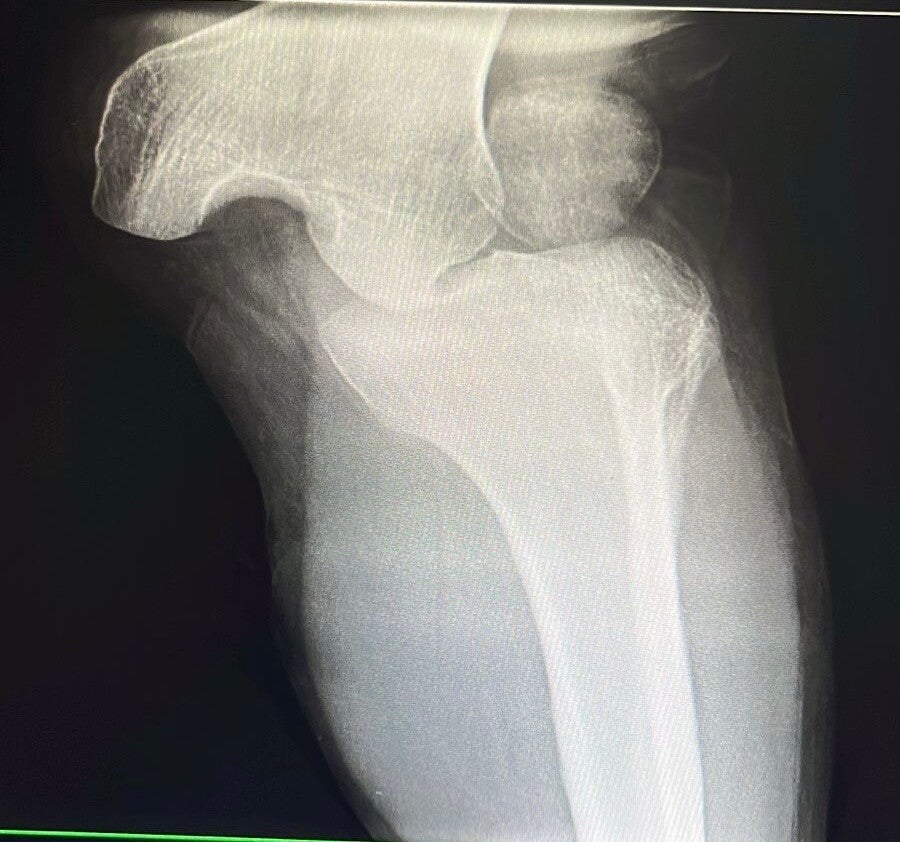

Lesiones musculoesqueléticas

Valoración experta de lesiones en rodilla, columna, hombro y cadera. Recupera tu movilidad y calidad de vida con nuestros tratamientos especializados.

Urgencias médicas

Atención inmediata y efectiva para fracturas, luxaciones, infecciones y otras urgencias médicas que requieran acción rápida.